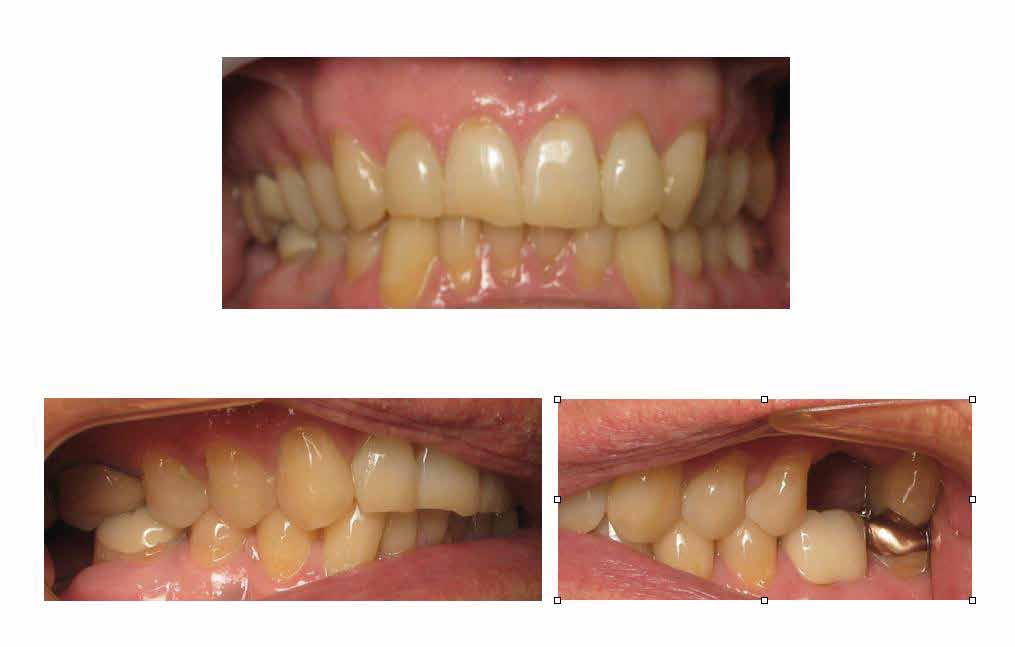

Positive findings from his health history were high blood pressure, stroke, asthma, hepatitis, and frequent awakenings at night. Our clinical findings at time of examination were: BMI 31.07, B.P. 166/100, Pulse 64, Respirations 16, Temperature 98.2. Orthopedic mandibular ranges of motion were 56 mm without pain, left and right lateral movements of 10 mm, and 9 mm of protrusion. Dental examination demonstrated molar class one occlusion, with 4 mm of overjet and overbite, with worn dentition (bruxism), see Figure 3.